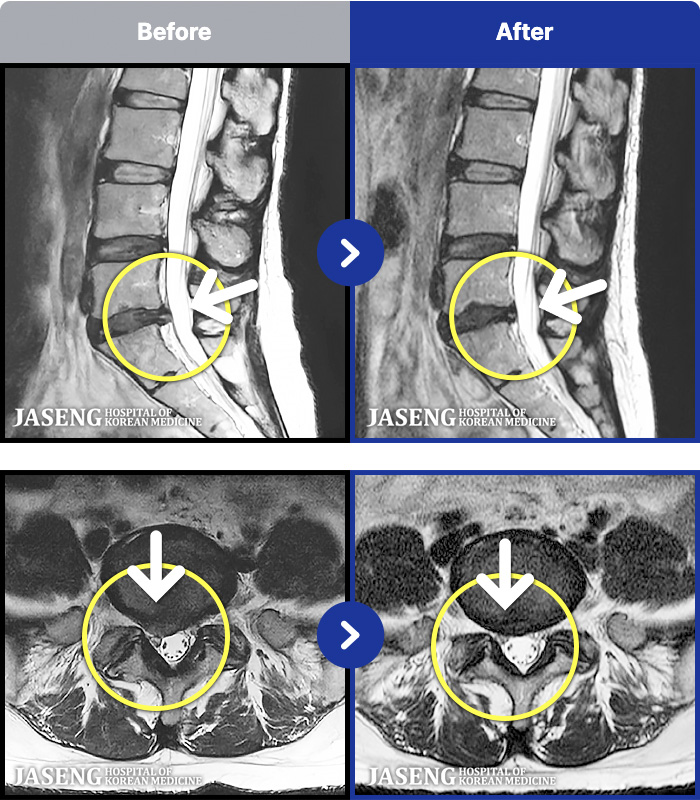

188 MRI ũ ʸ Ȯϼ.

ȯںп Ǹ ǿ ԿǾ, ο ġ ۿ Ƿ ġḦ Ͻñ ٶϴ.